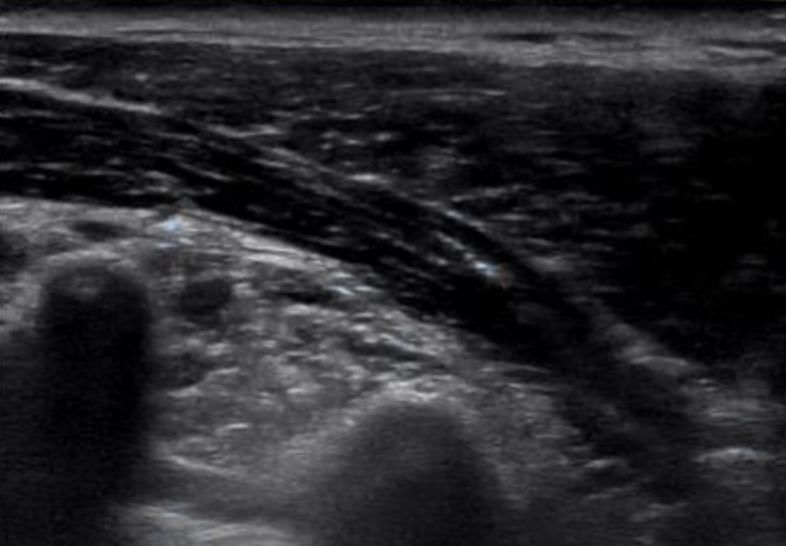

そして、こちらが肩コリの症状を感じている方のエコー画像です。

両方とも同じような場所をみているのですが、

下の画像の方が、画面下側の白っぽさが強いと思いませんか?

ごく簡易的に説明すると、

エコーは硬いものほど白く映る装置になります。

なので、凝って固くなっている部分が白く厚く映るのではないかということです。

これが肩コリの正体ではないかと考えています。

専門用語で、この白くなった部分をスタッキングファシア(ファシアの重積)といいます。

実は、この下には肺があるので、

あまり深く刺すのができない場所なんですが、

エコーで肺の位置が確認できるので、

深いところにあるコリにも安全にアプローチができるのです。